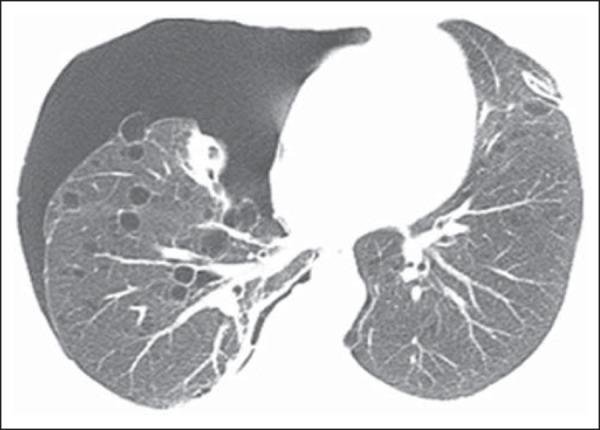

结节性硬化症的影像学:图文综述

Imaging of tuberous sclerosis complex: a pictorial review.

Tuberous sclerosis complex (TSC) is a genetically determined hamartomatous neurocutaneous disease with high phenotypic variability. TSC is characterized by widespread hamartomas and benign, or rarely malignant, neoplasms distributed in several organs throughout the body, especially in the brain, skin, retina, kidney, heart, and lung. Common manifestations include cortical tubers, subependymal nodules, white matter abnormalities, retinal abnormalities, cardiac rhabdomyoma, lymphangioleiomyomatosis, renal angiomyolipoma, and skin lesions. The wide range of organs affected by the disease implies that TSC1 and TSC2 genes play important roles in the regulation of cell proliferation and differentiation. Although recent advances in treatment have improved morbidity, the prognosis remains quite poor and nearly 40% of patients die by the age of 35 years. Imaging is important in the evaluation of TSC because of its role not only in presumptive diagnosis, but also in defining the full extent of involvement. This information allows a better understanding of the behavioural phenotype, as related to lesion location. Imaging also contributes to treatment planning. This pictorial review describes common and uncommon imaging manifestations of TSC.

摘要